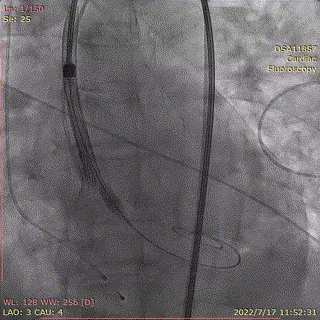

输送系统顺滑缓慢过弓,跨瓣,AV26瓣膜瓣环下0mm定位释放。

输送器跨瓣到位

第一次定位

0位缓慢释放